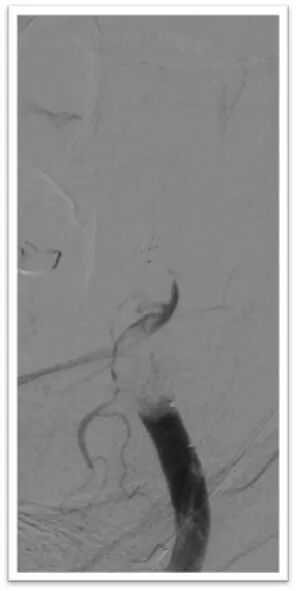

图4:DSA提示主动脉弓为牛角弓,左侧颈总动脉发自头臂干动脉,右侧颈内动脉造影提示前交通动脉开放,呈双干大脑前动脉,左侧大脑前动脉通过软膜支向左侧大脑中动脉供血区域代偿,双侧椎动脉均势供血,左侧大脑后动脉通过软膜支向前代偿供血;左侧颈总动脉闭塞,残端呈杯口状,近端可见白色血栓影,初步考虑栓塞性闭塞。